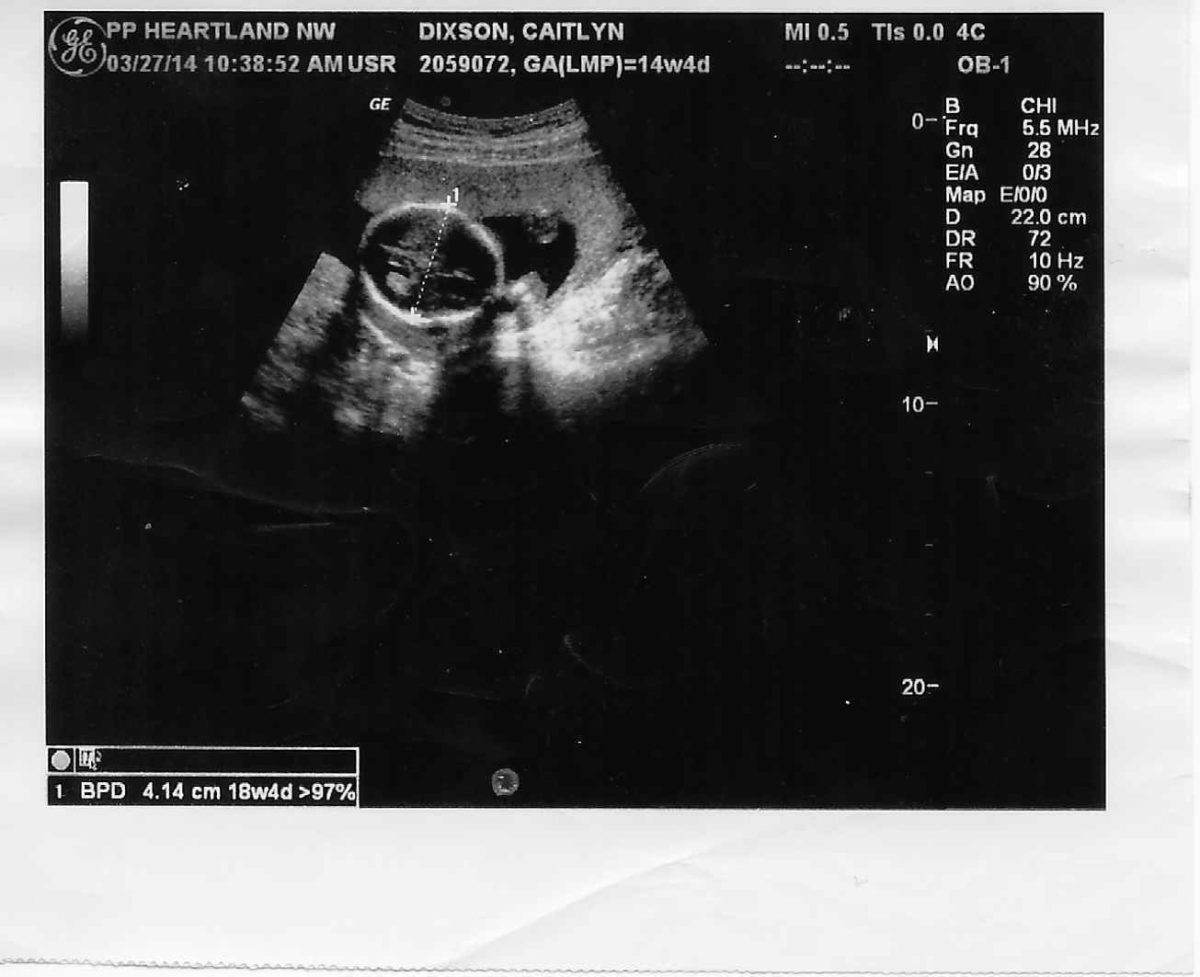

State Micaiah Bilger Jun 17 2020 914AM Des Moines IA. Planned Parenthood Takes Aim at Indiana Ultrasound Law Tim Bradley November 16 2016. Doctors in Planned Parenthood and other abortion clinics use ultrasounds to determine the age and size of the baby or to guide them as they perform abortions.

A federal judge heard arguments on November 9 on Planned Parenthoods challenge to an Indiana law requiring that an ultrasound be performed on a woman seeking an abortion at least 18 hours before the abortion is scheduled to take place. From the information I have read Planned Parenthood uses ultrasound for the abortion procedure they will not perform an ultrasound for someone wantingintendingconsidering keeping their baby. No they do not.

Planned Parenthood uses ultrasound to determine a babys age and position in the womb before it kills her. They rarely use them otherwise. ADVERTISEMENT The abortion business is criticizing an Iowa bill that ensures abortion facilities give women the opportunity to see their unborn babies on an ultrasound and hear their babys heartbeat at least 24 hours prior to.